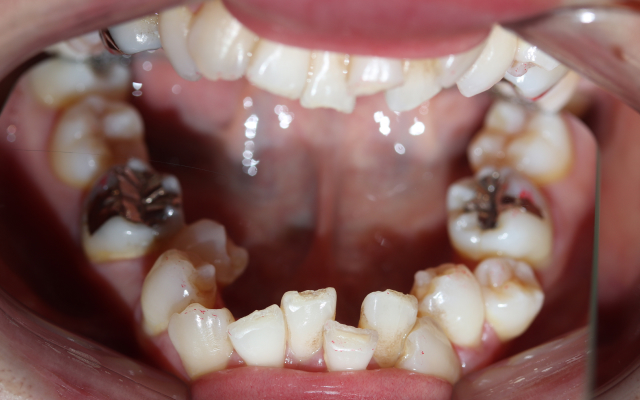

case. 01

インビザライン矯正の症例

before

after

30代 女性 叢生(そうせい), 交叉咬合(こうさこうごう)

施術概要

マウスピース矯正は、1日20時間以上マウスピースを装着する事により歯並びの矯正を行う事が出来る治療です。歯を動かしていく段階で1週間毎に新しいアライナーに交換し、少しずつ歯並びを綺麗にしていきます。

金額

616,000円(税込)

期間・回数

1年5ヶ月

リスク・副作用

全ての方で、疼痛、咬合痛、歯根吸収、歯根露出が生じる可能性があり。マウスピースを装着できなかった場合、予定通りに歯が動かない可能性があります。